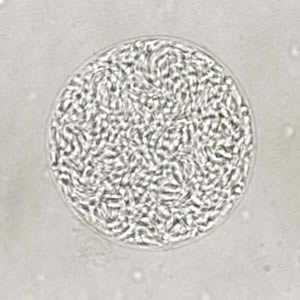

Toxoplasma gondii cyst, unstained.

Figure A: Unstained cyst of T. gondii.